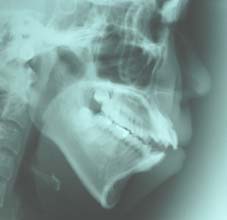

2.上顎前突(出っ歯) 上の前歯がかなり出ていています

治療前